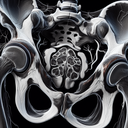

МРТ кульшових суглобів

Магнітно-резонансна томографія (МРТ) кульшових суглобів — це неінвазивний метод візуалізації, який використовується для детального обстеження цієї частини тіла. Він дозволяє отримати високоякісні зображення м'яких тканин, хрящів, суглобів, сухожиль і кісток. ### Переваги МРТ кульшових суглобів: - **Висока точність**: Дозволяє виявити навіть незначні патології...